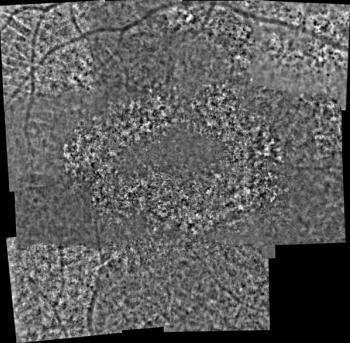

John B. Miller, MD, discusses widefield swept-source OCTA and its use in monitoring biomarkers in diabetic retinopathy.